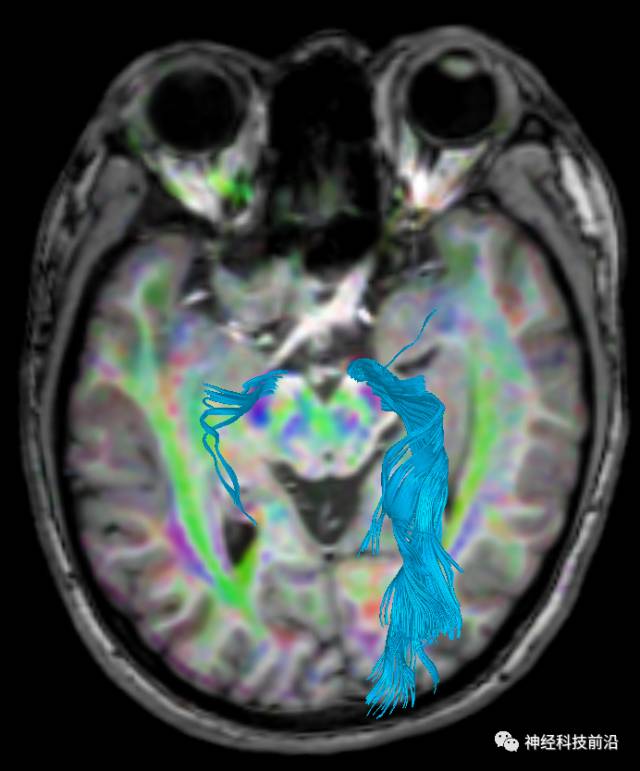

脑干内高信号为一近环形纤维束,其作用尚待研究。

上述纤维束与小脑中脚的位置毗邻